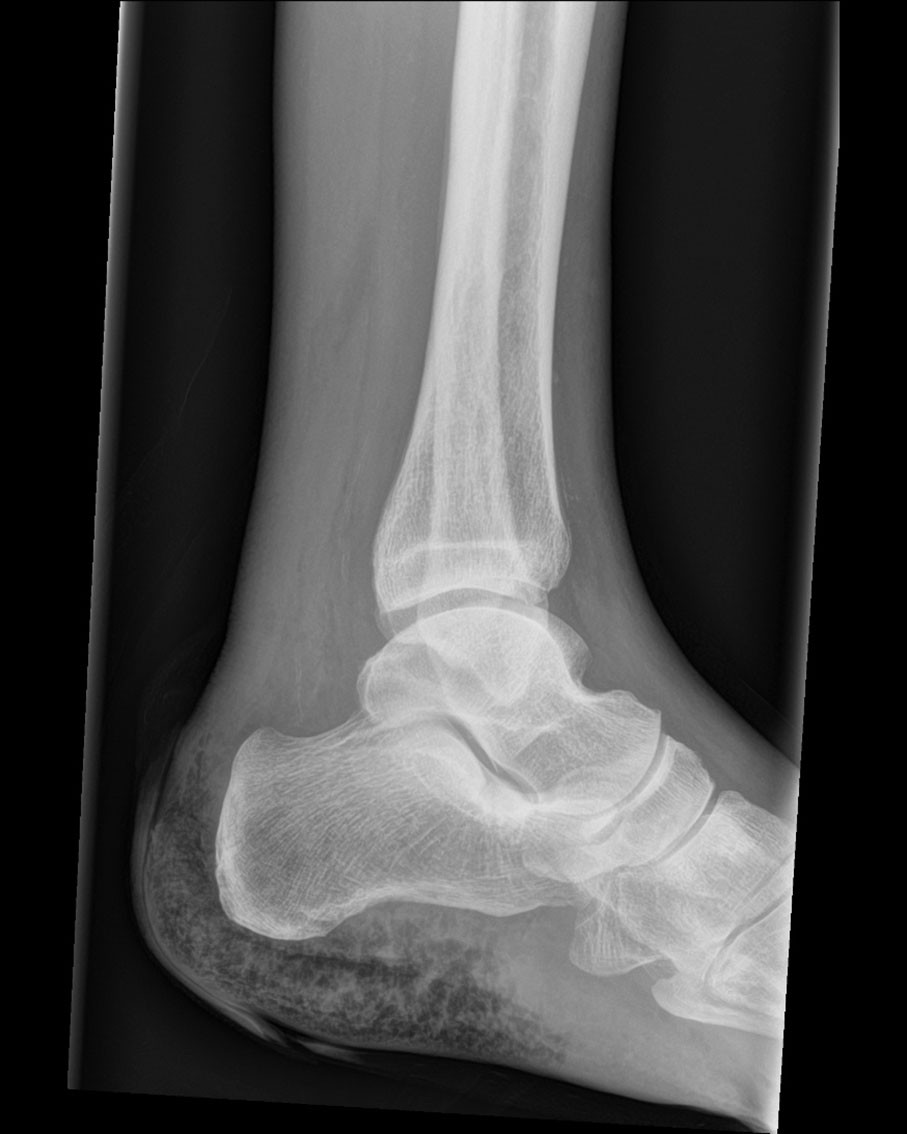

This X-ray image of the left ankle shows gas in the soft tissue around the heel. The patient, a man in his seventies, was admitted to the emergency department with fever and pain in the left foot. He was known to have colon cancer with spread to the peritoneum and lungs. Four years prior to this admission, he had undergone right hemicolectomy, but had declined any further curative treatment. Three days prior to admission, he developed pain in the left ankle and, according to his spouse, he became confused and his condition declined further. There was no information about trauma, recent wounds or rash.

The following day, there was growth of Clostridium septicum in two anaerobic blood culture bottles. At this time, the blister over his heel spontaneously ruptured, releasing extremely foul-smelling fluid. There was no definite palpable crepitus. X-ray of the left ankle revealed soft tissue emphysema around the heel. Antibiotic treatment was switched to intravenous piperacillin/tazobactam 4 g/0.5 g four times daily. One and a half days after admission, the patient underwent supramalleolar guillotine amputation as a life-saving procedure under general anaesthesia, and vacuum-assisted closure therapy was initiated. One week later, definitive below-knee amputation of the left limb was performed with primary closure. After a further week of observation, the condition of the amputation stump was unremarkable. The patient was discharged for a short-term admission in a municipal institution and referred for rehabilitation to have a prosthesis fitted.